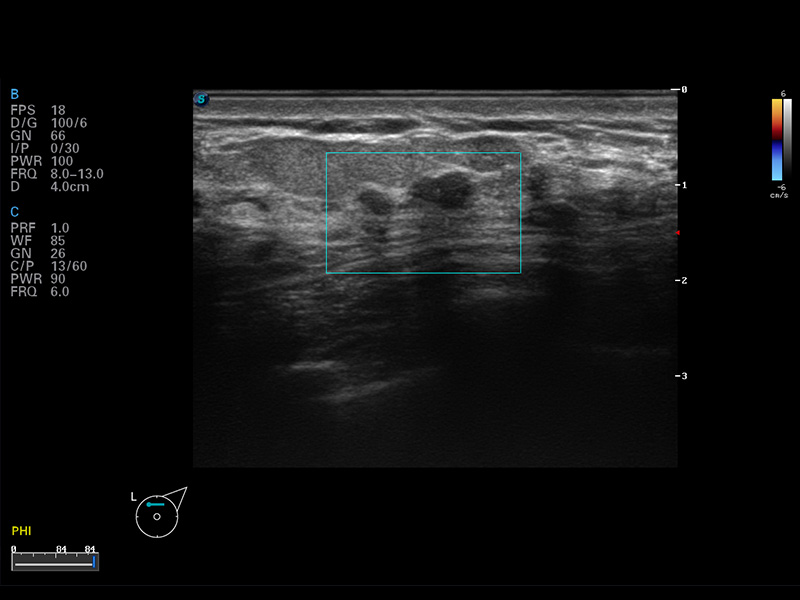

S8 EXP便携式彩色多普勒超声诊断仪是米兰官方网站研发的高端全身应用型便携彩超。高通道的VIS平台融合可视化(Visual)、智能化(Intelligent)和人性化(Smart)的特点,配以米兰官方网站自主研发生产的探头大家族,使您能够快速、准确的获得病人信息,提高工作效率的同时减轻疲劳。

成像技术

实时宽景成像